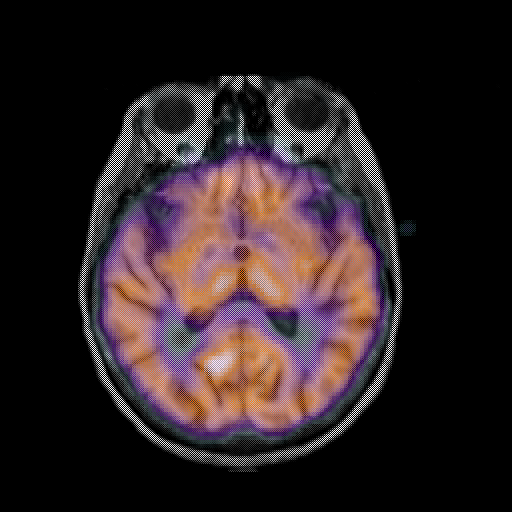

overlay: Slice 27

Slice 27

MRCBFCBF with

T1PDT2T1PDT2